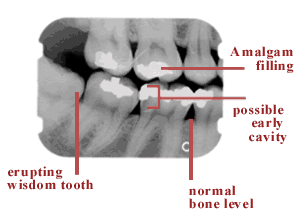

For example, x-rays can show the condition of your teeth, their roots, jaw placement and the overall composition of your facial bones. X-rays can help your dentist determine the presence or degree of periodontal (gum) disease, cavities, abscesses and many abnormal growths, such as cysts and tumors. X-rays also can show the exact location of impacted teeth and teeth that have not yet fully developed. Finding and treating dental problems at an early stage can save time, money and unnecessary discomfort. If you have a hidden tumor, x-rays may even help save your life.

- Periapical x-ray gives the dentist an image of the entire tooth, including the roots. With periapical x-rays, dentists evaluate a particular tooth’s root structure and bone level and also can detect cysts and abscesses.

- Panoramic x-ray allows your dentist to see the entire structure of your mouth (all of your upper and lower teeth and parts of your jaw) in a single image, which a bitewing or periapical x-ray cannot show.